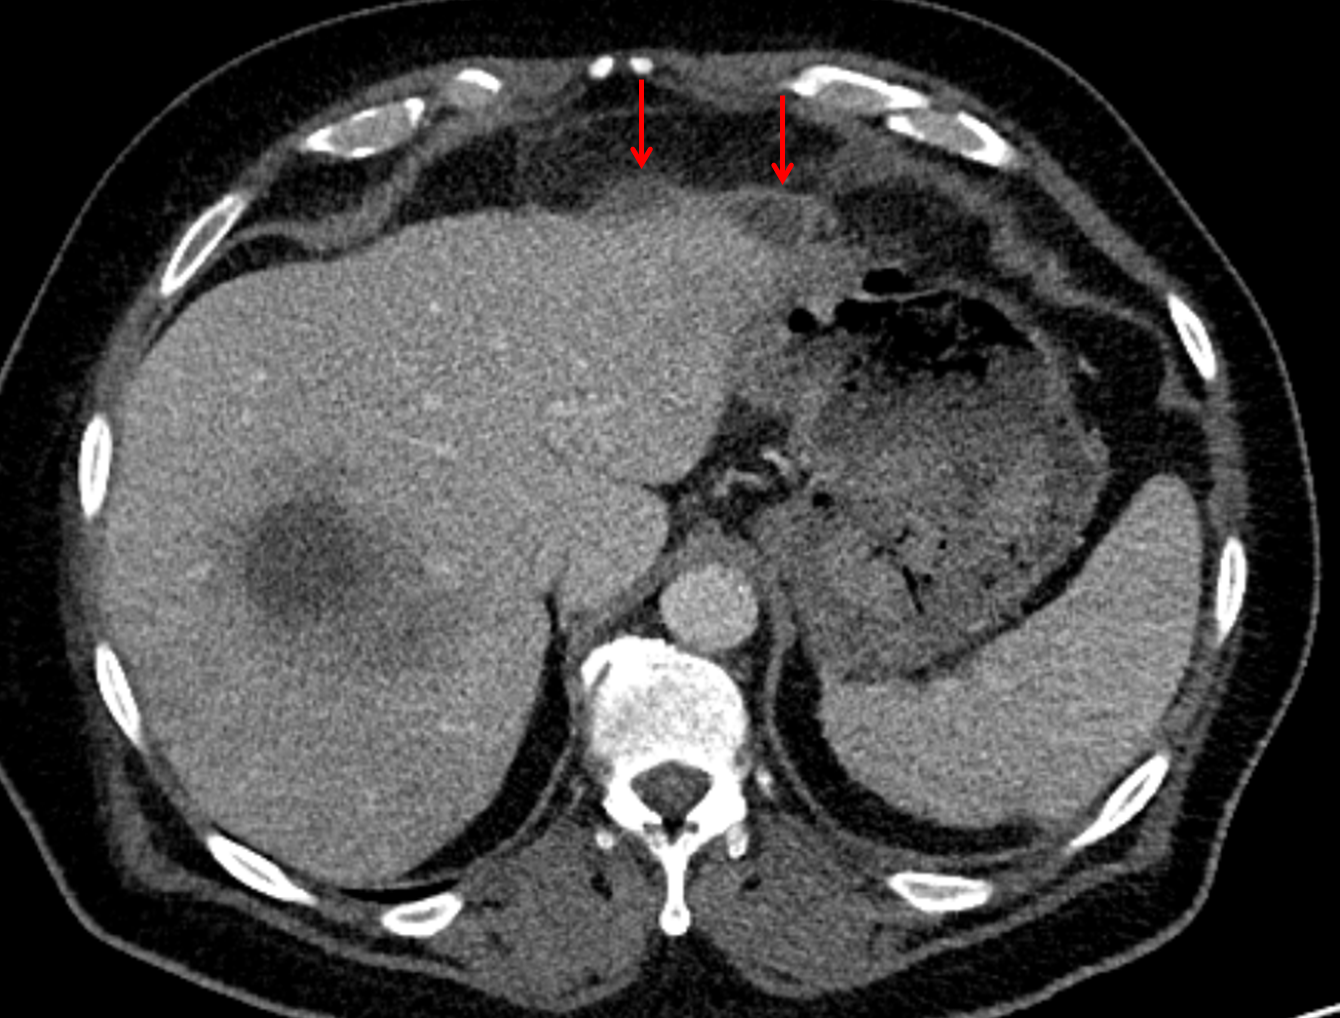

• Peripherally enhancing subcapsular collections along the anterior margin of the left hepatic lobe measuring 3 x 1 cm and 2 x 1 cm

• Mild mural thickening of a segment of the sigmoid colon with adjacent fat stranding and a 1.5 cm fluid and gas collection along the tip of an inflamed diverticulum

• Loss of the normal fat plane between this collection and adjacent loops of small bowel, which demonstrate mural thickening

Acute sigmoid diverticulitis complicated by a small contained perforation and a large abscess in the right hepatic lobe. Additional small subcapsular abscesses along the anterior margin of the left hepatic lobe.

Additionally, loss of the normal fat plane between the peridiverticular collection and adjacent thickened loops of small bowel raises the potential for an enterocolonic fistula.

Hepatic abscess showing the double target sign with low density internally surrounded by a thin inner enhancing rim (red arrow) and ill-defined outer low density rim (yellow arrow). Blue arrow indicates an internal septation. Red arrows: additional smaller subcapsular abscesses. Red arrow: focal contained perforation associated with diverticulitis.